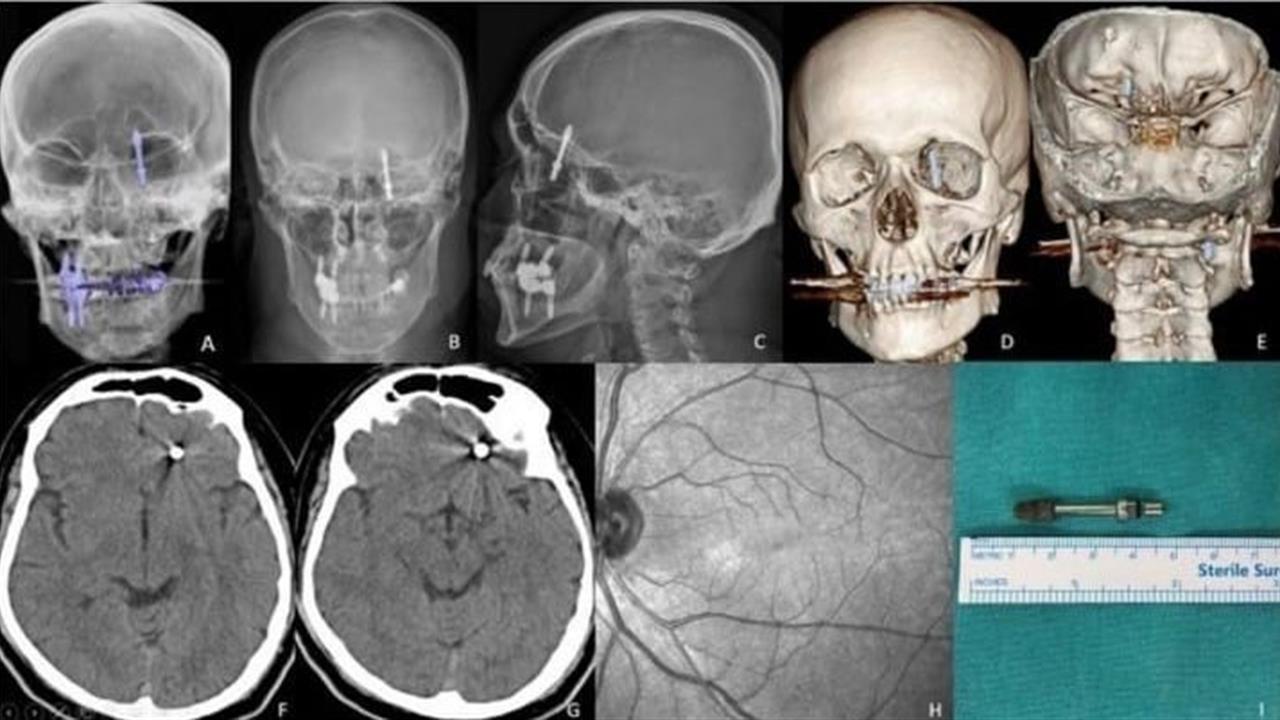

Bursa'da Ramazan Yılmaz, beynine yerleştirilen implant sonrası büyük bir travma yaşadı. Hem sağlığını hem de işini kaybeden Yılmaz, ödediği muayene ücretinin iadesini talep etti ancak bu isteği reddedildi. İki yıldır mahkemeden bir duruşma tarihi alamayan Yılmaz, "Beynime implant saplandı ama kimse sorumluluk almıyor" diyerek yaşadığı çaresizliği dile getirdi.